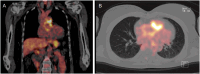

Case history: A 64-year-old female patient with a history of myalgia and recurrent joint swelling presented to our hospital. Initially suspected for rheumatoid arthritis, the patient underwent a series of orthopedic and rheumatologic treatments, including prednisolone and methotrexate. Subsequent history revealed a Ross operation in 2014 and a PET-CT was suspicious of a biological valved conduit infection leading to surgical replacement. Utilizing fluorescence in situ hybridization (FISH) diagnostic techniques, DAPI, Kinyoun and Ziehl-Neelsen staining, mycobacterial infection was confirmed in both the prosthesis and adjacent muscle tissue. Molecular methods identified a mycobacterium most closely related to the M. chelonae/abscessus complex indicating an association to a previously described outbreak of M. chelonae contaminated heart valves. Antimycobacterial therapy was initiated and the patient remains stable at the time of writing. To date, all mycobacterial cultures remained negative.

Conclusions: Non-tuberculous mycobacteria (NTM) are rare and possibly underdiagnosed pathogens in infections of bioprosthetic flap bearing conduits. Mycobacterial foreign-body infections can manifest many years after implantation. As NTM can be difficult to detect, molecular identification methods are of particular importance. Here, modern imaging, molecular and microscopic techniques might be of special use in diagnosing prolonged prosthetic graft infections.